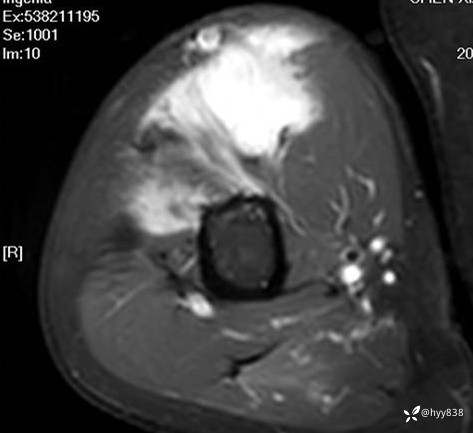

MRI AXI T1WI+T2WIfs

AXI T1WI+T2WIfs

CE